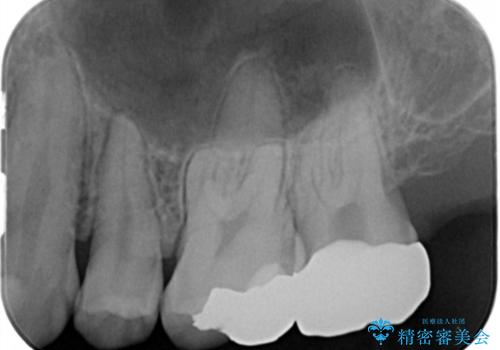

- 奥歯のザラザラが気になり、白い被せ物をしたいとのことで来院。

レントゲンや拡大鏡で確認をしたところ歯の表面は粗造になっていたが

う蝕があるわけではないので以下の提案を行った。

歯の表面が粗造なのは虫歯ではないが

歯の表面が溶けはじめて、虫歯になりやすい状態になっています。